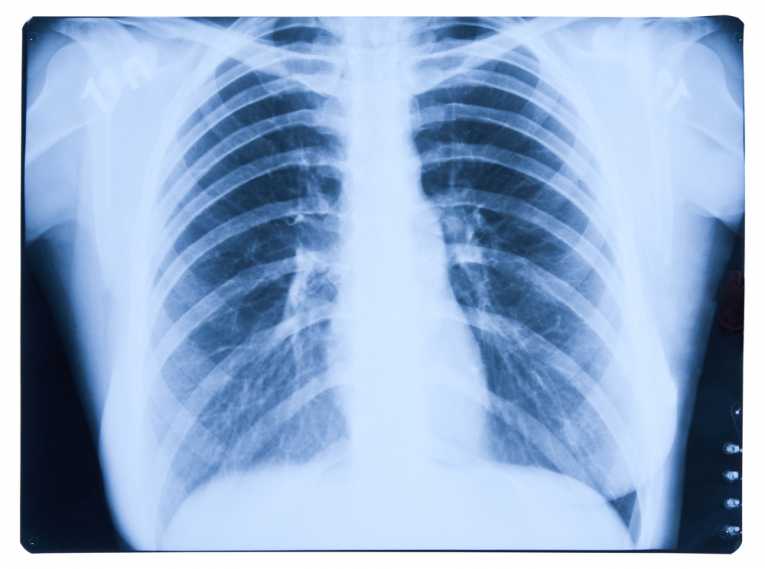

The term COPD covers various diseases of the lungs which cause airway obstruction and narrowing. The most common are chronic bronchitis and emphysema. Symptoms of these are the inflammation of the bronchi, which carry oxygen through the lungs and loss of elasticity of the alveoli, which transfer oxygen to the lungs. These symptoms in turn cause the narrowing of the airways and difficulty breathing associated with COPD.

A review of research over the past twenty years was conducted. The papers were primarily focussed on the link between COPD and lung cancer development as well as the importance of early COPD detection for prevention of lung cancer. It was found that the chances of developing lung cancer increase by 0.8% when patients also have COPD as opposed to those who do not.